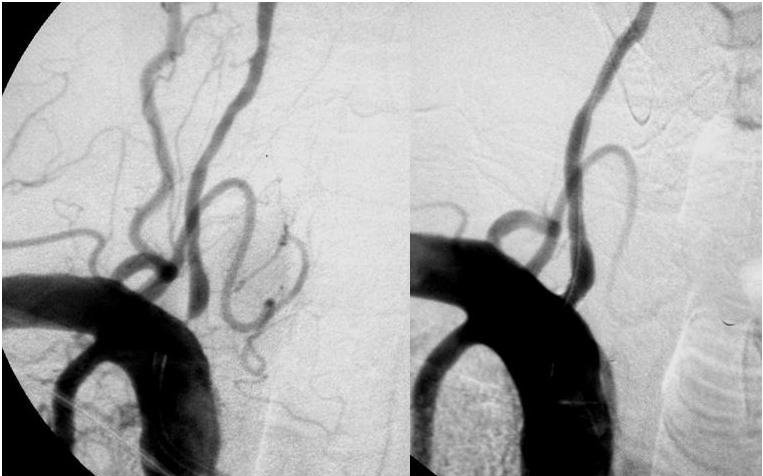

Stents en las arterias vertebrales: se precisan más estudios

En pacientes con estenosis sintomáticas en el territorio vertebral el tratamiento con stents no fue superior al manejo médico óptimo. Neurology, 19 de septiembre de 2017